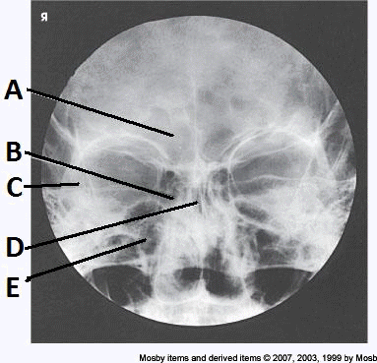

____ 10. Examine the image of the paranasal sinuses below. The letter D labels the:

a. crista galli

b. vomer

c. cribriform plate

d. perpendicular plate of the ethmoid bone

bb. vomer

____ 13. Examine the image of the paranasal sinuses below. The letter A labels the:

a. sphenoid sinuses

b. frontal sinuses

c. ethmoid sinuses

d. maxillary sinuses

bb. frontal sinuses

____ 32. Examine the image of the paranasal sinuses below. The letter A labels the:

c. crista galli

d. ethmoid sinuses

____ 37. Examine the image of the paranasal sinuses below. The letter F labels the:

a. maxillary sinuses

b. sphenoid sinuses

d. pharynx

dd. pharynx

____ 61. Examine the image of the paranasal sinuses below. The letter C labels the:

a. petrous ridge

c. sphenoid sinuses

d. condyle of the mandible

aa. petrous ridge

____ 84. Examine the image of the paranasal sinuses below. The letter A labels the:

b. ethmoid sinuses

d. frontal sinuses

dd. frontal sinuses

____ 136. Examine the image of the paranasal sinuses below. The letter B labels the:

a. frontal sinuses

b. maxillary sinuses

d. sphenoid sinuses

cc. ethmoid sinuses

____ 174. Examine the image of the paranasal sinuses below. The letter E labels the:

c. frontal sinuses

aa. sphenoid sinuses

____ 184. Examine the image of the paranasal sinuses below. The letter B labels the:

aa. maxillary sinuses

____ 191. Examine the image of the paranasal sinuses below. The letter C labels the:

a. ethmoid sinuses

c. petrous ridge

bb. maxillary sinuses